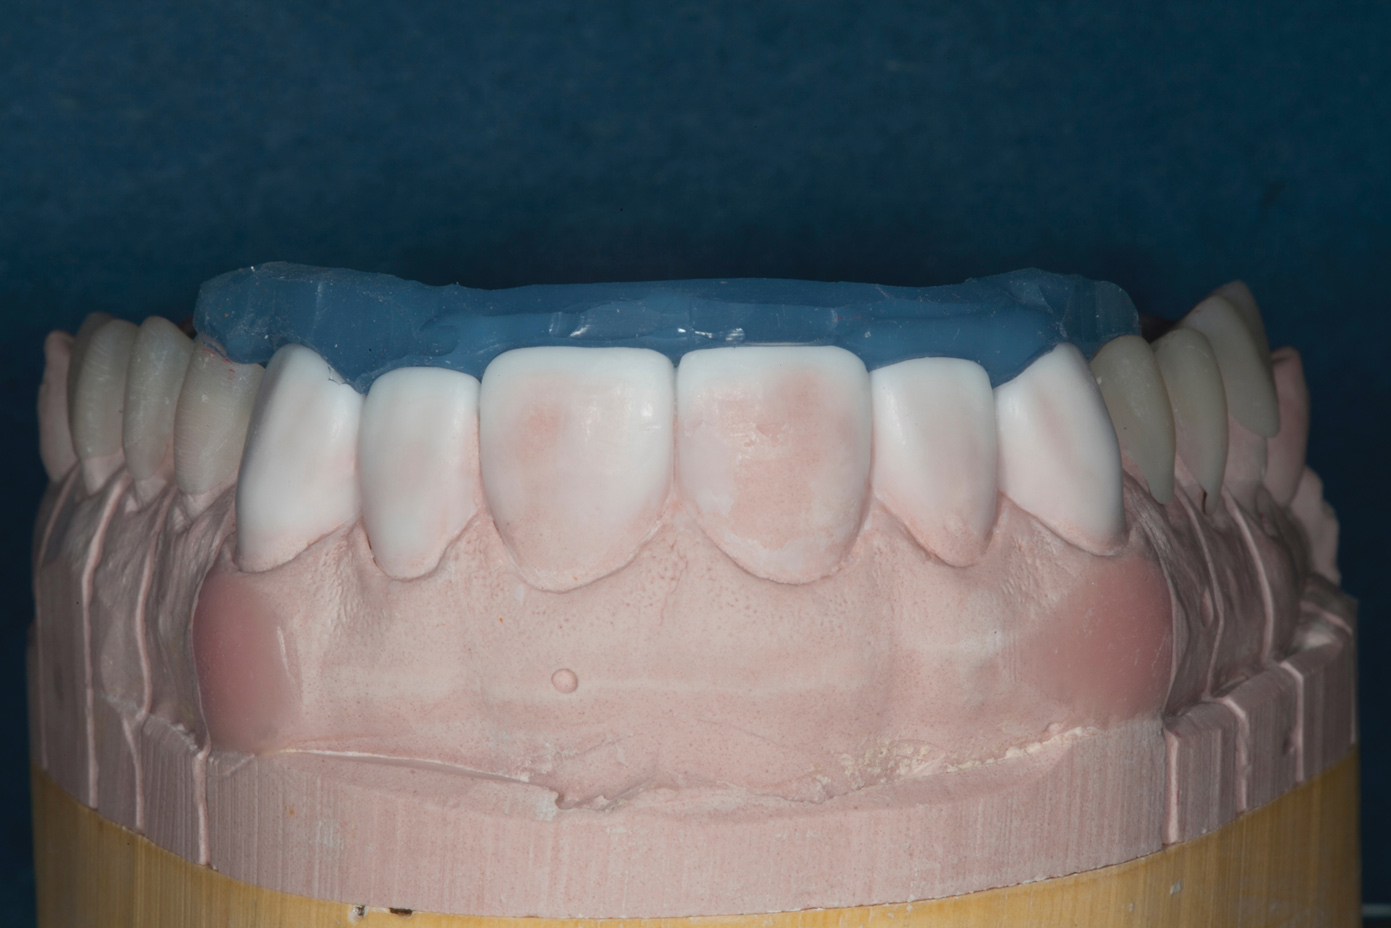

Fig 6. Fitting of prefabricated posterior units.

Figure 6

Treatment

Accurate vinyl polysiloxane impressions (Take 1, Kerr Corporation; kerrdental.com) were taken of the upper and lower arches. Two sets of models were obtained and mounted in a Panadent articulator (Panadent Corporation; panadent.com). A diagnostic wax-up to close the posterior open bite and incorporate the desired esthetic changes was carried out on one of these sets. The posterior waxed-up surfaces were then duplicated with a clear silicon matrix (RSVP, Cosmedent; cosmedent.com) in quadrants. These matrices were loaded with a slightly warmed microhybrid composite (Four Seasons, Ivoclar Vivadent; ivoclarvivadent.com) and seated onto the corresponding second model, which had been isolated with a separating agent. Warming the composites increases monomer conversion, thereby decreasing curing time and shrinkage.13 Once fully cured, the occlusion was adjusted, and the onlays could easily be separated from the models. (The author acknowledges that with today's technology, she would probably opt for a millable composite; a laboratory-produced, long-term provisional material; or a direct-injectible, high-strength composite and a matrix technique.)

Following caries treatment and tooth preparation (Figure 6), teeth Nos. 4 through 13 were restored with direct composite veneers in stages (Figure 7 through Figure 9). Using a hybrid composite for the lingual shelf and dentin layer provides wear resistance and strength for the restoration.14,15 (The lowest wear rates for restorations and the opposing dentition occur with metal alloys, machined ceramics, and microfilled hybrid resin composites. Any adjusted and unpolished porcelain surface would elicit the most wear on the opposing teeth.11)After the composite veneers were finalized, a monolithic lithium disilicate crown was placed on tooth No. 12 during a subsequent appointment, and occlusal equilibration was carried out. Final photographs were taken a couple of weeks later (Figure 10 through Figure 14).